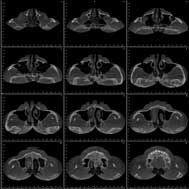

Un

bilan des Sinus de la face qui permet |

| d’apprécier l’état

des sinus : transparent ou foyer infectieux |

| d’apprécier l’état de la cloison

nasale |

| d’apprécier l’épaisseur de

la muqueuse des cornets |